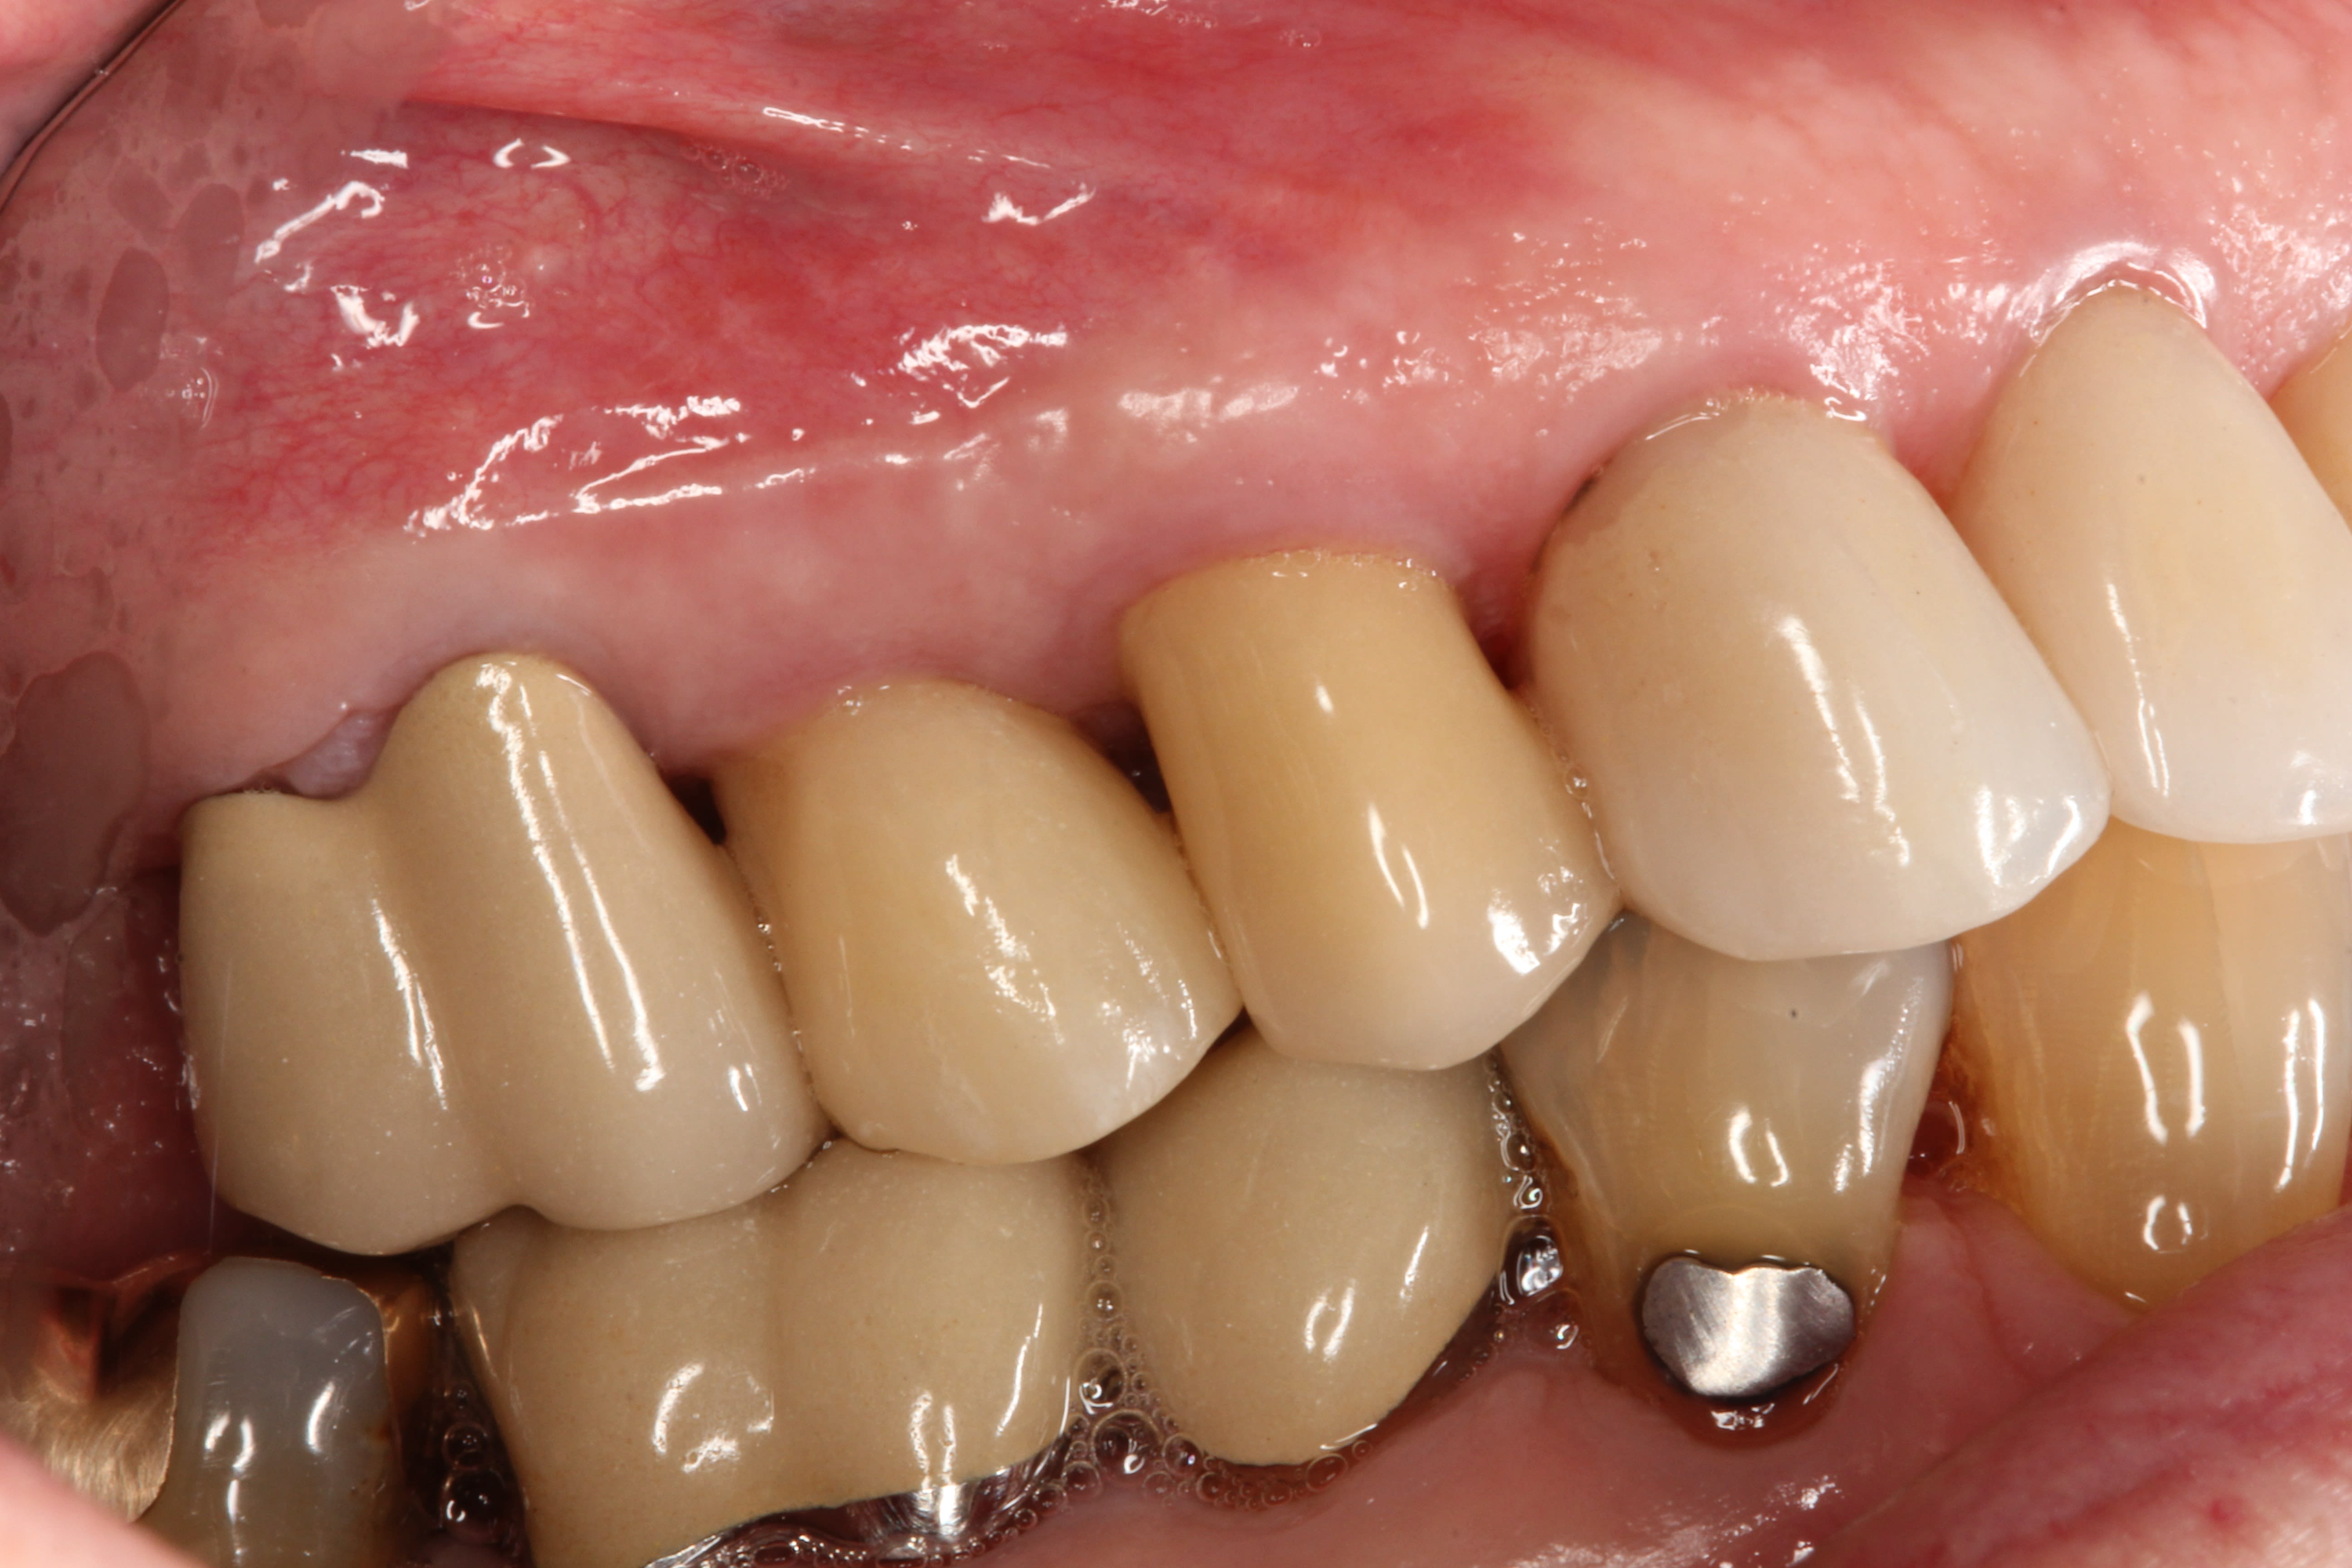

A healthy 67-year-old nonsmoking Caucasian woman presented to one author’s (KGM) periodontal/prosthodontic practice in January 2012 with a symptomatic maxillary right lateral incisor (tooth No. 7). Her biotype was deemed to be within normal limits, with the attached tissue thickness estimated to be greater than 2 mm, and there was no bleeding on probing (Figure 11).

The final impression (closed tray) was obtained in April 2012. The final ceramic crowns (IPS e.max Ceram) and custom porcelain-veneered, regular-diameter (RD) UCLA abutments (Genesis; and Creation CC, Jensen Dental, www.jensendental.com) (Figure 24, shown with PFM crowns and retention screws) were delivered in May 2012. Using a platform-switched connection, the abutments were torqued to 30 Ncm, the access holes sealed with Teflon, and the final crowns cemented with RelyX Unicem. Figure 25 through Figure 28 show the final IPS e.max Ceram crowns from periapical, facial, and incisal views, with a midfacial PD of 3 mm at the 18-month follow-up (Visit 7). A thick biotype is evident in Figure 26, as determined by the inability to detect the outline of the periodontal probe inserted below the restoration’s gingival margin.50 This image also demonstrates an excellent esthetic outcome.

Although Case 3 showed an 18-month PD of 3.5 mm on the facial aspect of implant position No. 9 (the greatest PD recorded at this timepoint), good gingival tone and excellent esthetics were also evident at this visit (Figure 26).